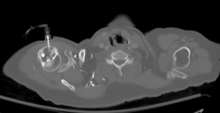

The needle is injected through the bone's hard cortex and into the soft marrow interior which allows immediate access to the vascular system. An IO infusion can be used on adult or pediatric patients when traditional methods of vascular access are difficult or impossible. In most cases, the antero-medial aspect of the upper tibia is used as it lies just under the skin and can easily be palpated and located. The anterior aspect of the femur, the superior iliac crest and the head of the humerus are other sites that can be used.